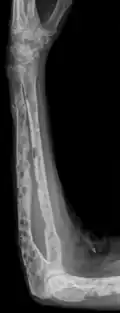

-

Bone marrow aspirate showing the histologic correlate of multiple myeloma under the microscope, H&E stain -

Plasmacytoma, H&E stain -

Micrograph showing myeloma cast nephropathy in a kidney biopsy: Hyaline casts are PAS positive (dark pink/red – right of image). Myelomatous casts are PAS negative (pale pink – left of image), PAS stain. -

Atypical plasma cell infiltrate with both Russell (cytoplasmic) and Dutcher (nuclear) bodies (H&E, 50x) -

Histopathology

A bone marrow biopsy is usually performed to estimate the percentage of bone marrow occupied by plasma cells. This percentage is used in the diagnostic criteria for myeloma. Immunohistochemistry (staining particular cell types using antibodies against surface proteins) can detect plasma cells that express immunoglobulin in the cytoplasm and occasionally on the cell surface; myeloma cells are often CD56, CD38, CD138, and CD319 positive and CD19, CD20, and CD45 negative.[21] Flow cytometry is often used to establish the clonal nature of the plasma cells, which will generally express only kappa or lambda light chain. Cytogenetics may also be performed in myeloma for prognostic purposes, including a myeloma-specific fluorescent in situ hybridization and virtual karyotype.

The plasma cells seen in multiple myeloma have several possible morphologies. First, they could appear like a normal plasma cell, a large cell two or three times the size of a peripheral lymphocyte. Because they are actively producing antibodies, the Golgi apparatus typically produces a light-colored area adjacent to the nucleus, called a perinuclear halo. The single nucleus (with a single nucleolus with vesicular nuclear chromatin) is eccentric, displaced by an abundant cytoplasm. Other common morphologies seen, but which are not usual in normal plasma cells, include: